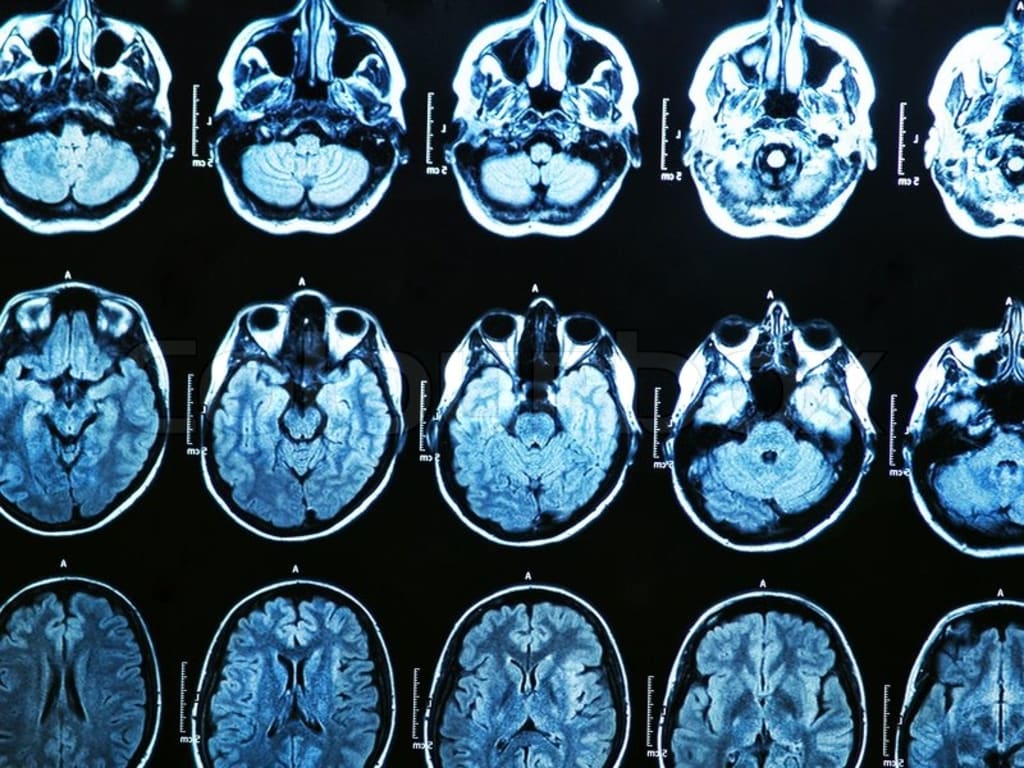

As researchers have found, it’s actually not. Emotions are produced by neurons spitting out chemicals, also called neural transmitters, into the receptors of other neurons, which are then processed and make you feel things like happy, sad, and angry. When your neurons are producing too much or too little of a certain chemical, it causes mental illnesses such as depression, OCD, schizophrenia, and bipolar disorder. This is why psychiatrists prescribe medication, it helps either inhibit or assist production of a specific set of chemicals depending on what the problem is. While your brain is much more complicated, this is just a basic idea of how it works. On a larger scale, in 2015, Dr. Amit Etkin and his team of researchers discovered through structural brain imaging that there is a structural difference in the brains of people afflicted with mental illness. Etkin found that in individuals struggling with schizophrenia, addiction, bipolar disorder, depression, obsessive-compulsive disorder, and anxiety disorders had shown loss of grey matter—the tissues in the brain containing the bodies of neurons—as opposed to their mentally healthy counterparts. The reduced amount of grey matter was found in three different areas in the brain: the dorsal anterior cingulate cortex, and the left and right insulas. Etkin and his team aren’t the only ones who’ve made significant progress on unravelling this issue, though. This year, researchers at Duke University have used magnetic resonance imaging, or MRIs, to examine communication between different areas of the brain. Their studies have shown a link to individuals whose visual cortex communicated less to the rest of the brain and their likelihood to be at greater risk for common mental illnesses.